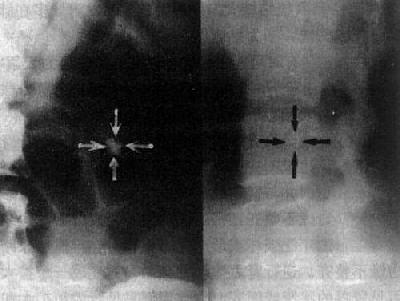

逆行肾盂造影,如注射压力过高会造成造影剂回流又称逆流或反流,入肾小管或血管周围等处,造成各种特殊的表现(图4-4-2)。应当避免造影剂回流。常见下数种回流:①肾小管回流,造影剂经乳头进入肾小管,表现为由肾小盏中心向皮质方向散布的放射状致密影;②肾窦回流,肾小盏穹窿部撕裂,造影剂回流入肾窦,表现为穹窿周围不规则角状或带状致密影,显著者出现一片不规则毛糙影;③血管周围回流,造影剂沿静脉周围间隙散布,表现为自穹窿向外走行的拱门状细条状影;④淋巴管回流,造影剂进入淋巴管,表现为纤细蜿蜒迂曲的线条影,向肾门方向行走。

图4-4-2 肾盂各种回流